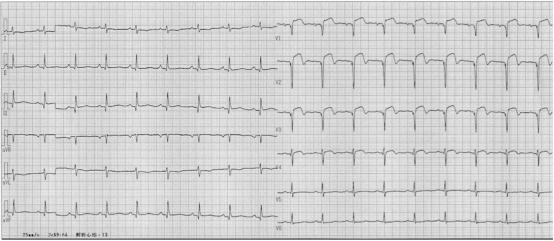

说罢,马修拿起了患者的心电图(图1),V1-V4导联ST段抬高,提示急性心肌梗死。

图1 入院心电图又有学生发问:“马老师,心电图既然已经诊断急性心梗,现在为啥不去做造影?”

急查电解质,血钾4.05mmol/L,心电图未发现QT间期延长、ST段动态变化,波仔把抢救经过告知了马修。

图5电风暴发作时的心电监护三